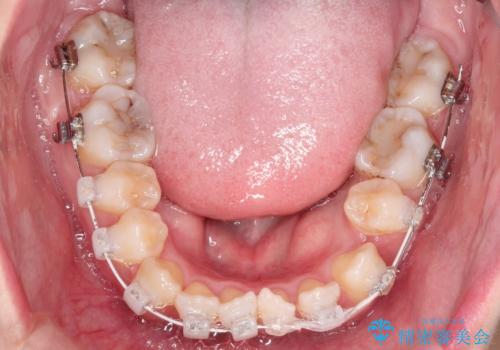

装置は表側のワイヤーを選択されました。

- 治療期間

- 1年11ヶ月